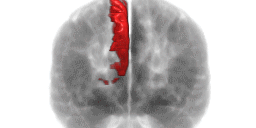

La recherche dans le domaine de la neuroéducation a permis de mettre en évidence l’efficacité de l’apprentissage par stratégie. C’est une approche plus active qui engage davantage le cerveau, en particulier une zone connue sous le nom de précunéus, située dans le cortex occipital, lié principalement à la vision. Cette zone du cerveau relie une « zone visuelle » à une « zone verbale » (cortex temporal), mais aussi à une autre zone dite « symbolique » (cortex parietal), et une dernière zone, dite « stratégique » (cortex préfrontal).

Le précunéus, une petite région située au sein du cortex occipital, a une grande importance pour l’apprentissage stratégique. Voyons comment il fonctionne:

Le précunéus, une région du cerveau située dans le cortex occipital, joue un rôle clé dans l’apprentissage par stratégie. Il relie plusieurs zones du cerveau, facilitant la création d’images mentales, l’interprétation de symboles et la planification de stratégies, ce qui favorise une meilleure compréhension et mémorisation.